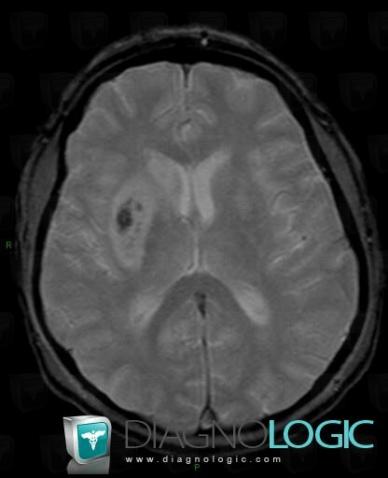

Cerebral infarction, Basal ganglia and capsule, MRI

Here is the specific information in the key image above:

- Diagnosis Cerebral infarction, Location(s) Basal ganglia and capsule, with gamuts DWI hyperintense lesion